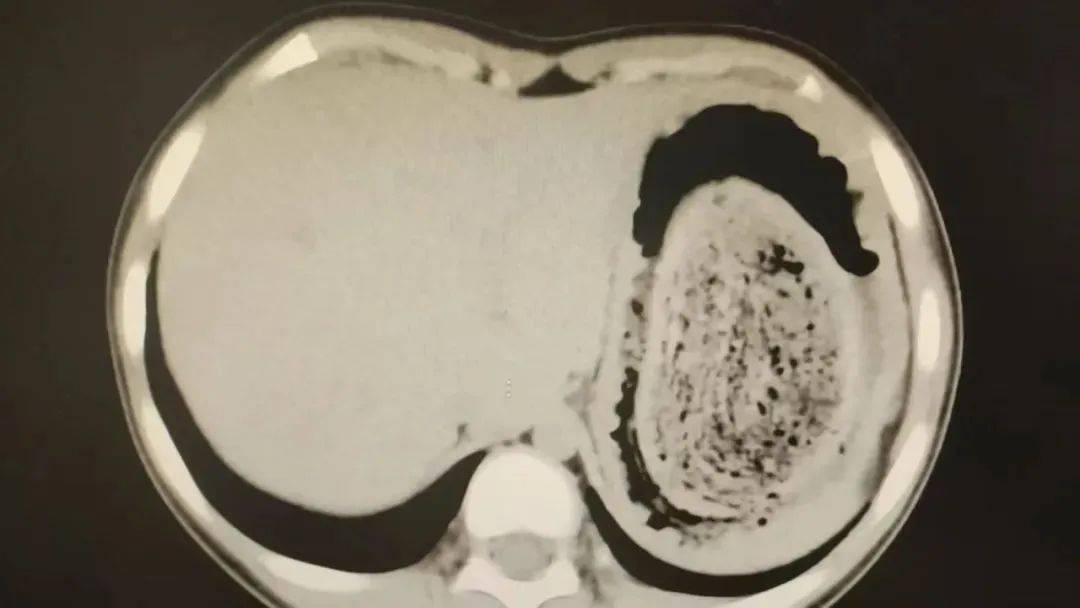

在胃镜帮助下,妮妮胃里的情况逐渐明了苏格兰超级联赛。一个滚圆黑色的毛发球混合着食物残渣占据整个胃腔,这些头发相互缠绕形成一个实心的“发石”,此外胃里还有一个鸡蛋大小的溃疡。

症结找到了,就是这个巨大的发石导致妮妮出现营养不良、贫血和闭经,当务之急就是取出“发石”,给胃进行“大扫除”苏格兰超级联赛。

头发缠绕在一起十分坚硬,体积巨大,胃镜尝试多次均难以取出,医护人员不得不采取开放手术的方式来取“发石”苏格兰超级联赛。

7月14日,武汉儿童医院肝胆肿瘤外科副主任医师朱真闯主刀苏格兰超级联赛。术中见妮妮胃部足有正常状态2倍大,切开胃壁后,一股酸臭味弥漫开来。

“发石”混杂着食物残渣,就像一个黑色的小西瓜苏格兰超级联赛。由于整个“发石”体积太大,为避免损伤胃壁,医生借助手术工具将“发石”切割、分解,再小心翼翼地分块取出。整场手术持续2个多小时,最终取出4斤头发碎片。

10岁女孩园园(化名)因持续3天的上腹痛伴呕吐被紧急送医苏格兰超级联赛。影像学检查结果显示,她的胃部存在一个巨大的团块状阴影,初步怀疑为异物堵塞。据家长回忆,园园从1年前开始就有偷偷吃头发的习惯,但家人并未重视,直到这次症状严重才意识到问题的严重性。

2024年10月,11岁女孩欢欢(化名)因腹痛难耐紧急送到医院,而就在两个月前,欢欢的父母发现她在拔自己的头发,偷偷吃掉苏格兰超级联赛。经检查,医生发现她胃腔和肠管里有大块的毛絮状结石,几乎占据整个胃部。最终,一块长38厘米、宽15厘米、厚10厘米的毛发结石被取出。